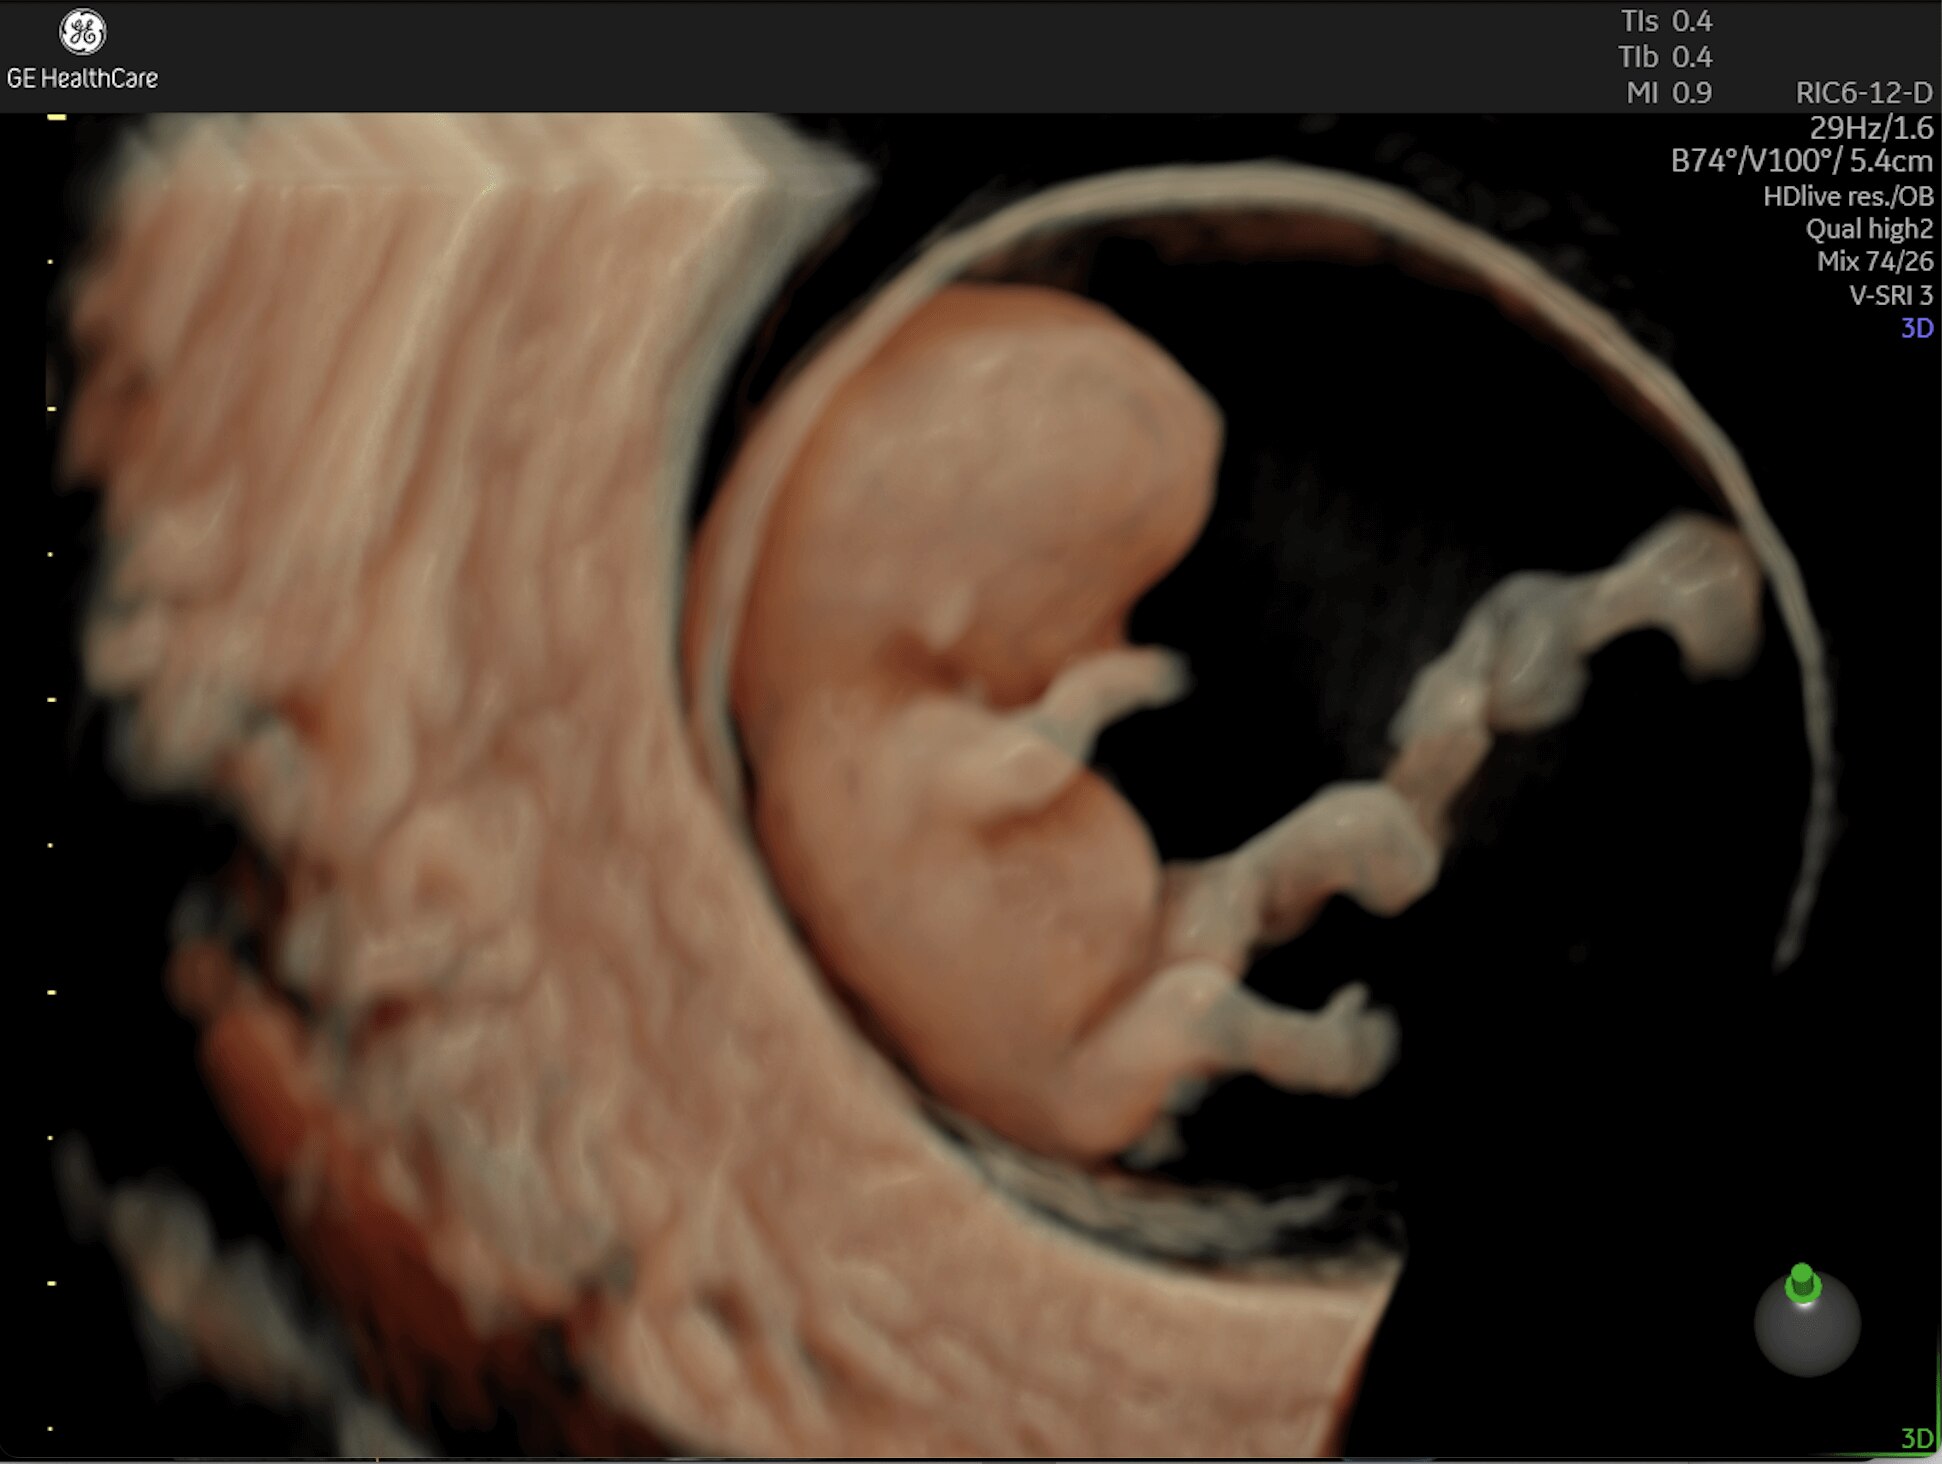

Early Detection

Critical Answers Sooner

Complex cases come with enough uncertainty. That's why the Voluson Expert 22 is specifically designed for in-depth assessment of complicated anatomy — with pioneering first trimester, fetal cardiac, gynecological, and other pivotal technologies that focus on early detection and intervention.